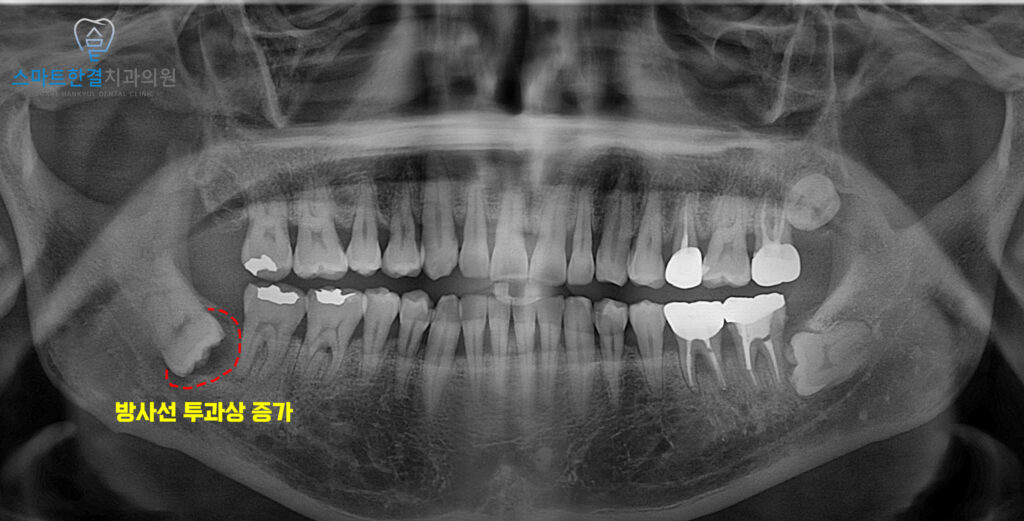

이후 1년 뒤 검진 위해

재내원 해주셨어요.

파노라마를 촬영해 보니,

1년전보다 사랑니 주위로

방사선 투과상이 증가하고

앞 치아의 통증과 함께

이상한 맛이 느껴진다고 하셨는데요.